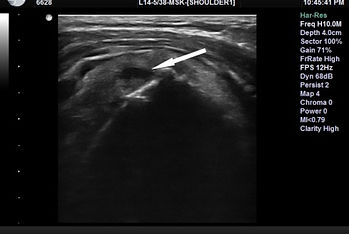

(본원에서 시행한 초음파상 극상건의 부분파열 소견)